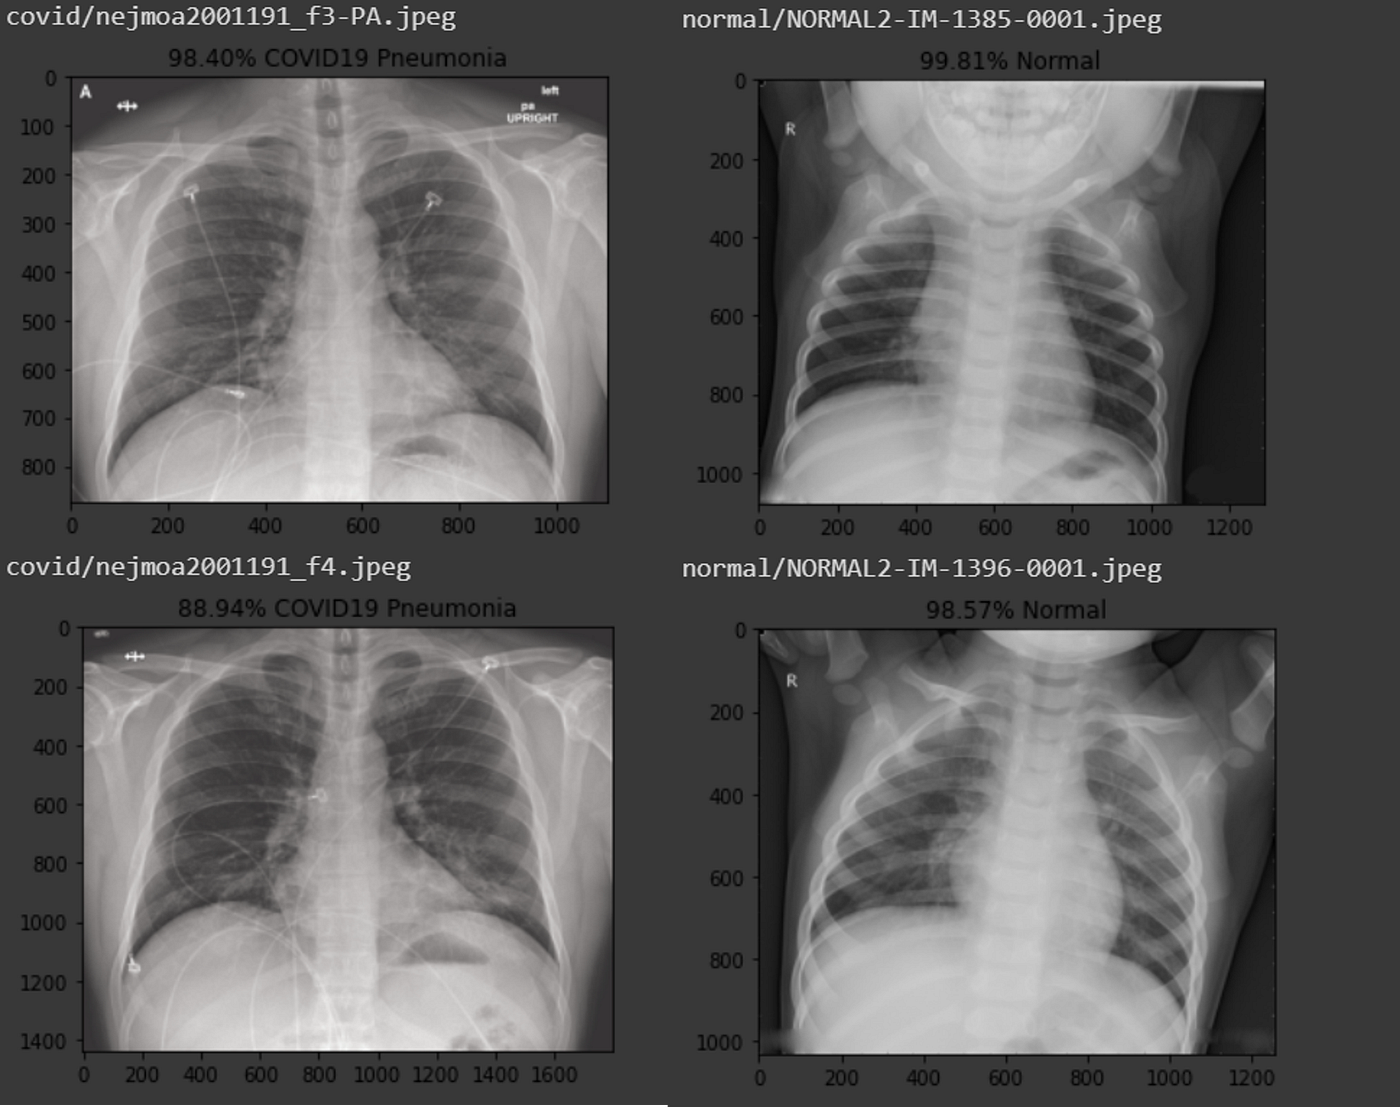

AIpowered radiology model diagnoses pneumonia in 10 seconds Medical

Detecting Pneumonia in Chest XRays Using Various Deep Neural Nets by How To Read A Pneumonia X Ray In fact every radiologst should be an. Pneumonia, which is defined as inflammation of the. in 2019, 2.5 million people died of ‘clinical’ pneumonia and pneumonia was the leading cause of death for children under 5. Dec 20, 2019 | 6 comments. Normal appearance in healthy individuals. Name, date of birth and unique identification. before proceeding to how. How To Read A Pneumonia X Ray.